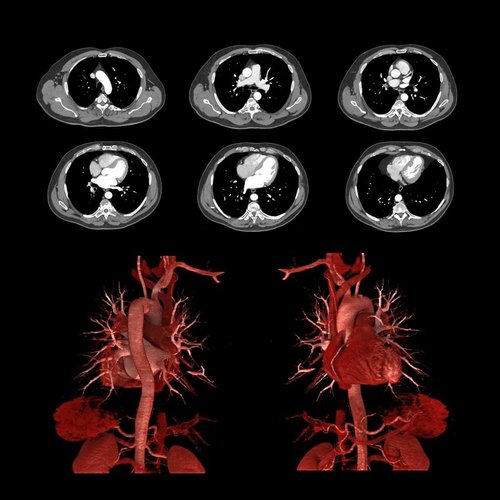

Bei dem Volumen-CT Aquilion One PRISM Edition von Canon Medical handelt es sich um einen einzigartigen HighEnd-Computertomographen. Er setzt während der DualEnergy-Akquisition und der Datenrekonstruktion neue Maßstäbe und greift in der spektralen Bildgebung auf die Deep-Learning-Rekonstruktion AiCE zurück.

Die Kombination lässt den Tomographen besonders in den Disziplinen von State-of-the-Art-Bildgebung, der Virtual-Non-Contrast-Bildgebung und dem Erstellen von Jodbildern sowie der Quantifizierung von Jod hervorstechen.

Mit AiCE, kurz für Advanced intelligent Clear-IQ Engine, kann der Aquilion One PRISM Edition besonders scharfe, klare und präzise Bilder in kürzester Zeit gewinnen. Die KI unterstützt die Reduktion von Bildrauschen auf ein Minimum und ermöglicht klare Aufnahmen mit sehr gut erkennbaren Strukturen auch bei niedrigem Kontrast. Gleichzeitig bringt sie eine automatische Anpassung des Kontrasts mit sich. Weiterhin ermöglicht sie eine schnelle kV-Umschaltung und eine patientenspezifische mA-Modulation, die wiederum mit einer Deep Learning-Rekonstruktion kombiniert wird, um eine hervorragende Energietrennung zu erzielen und Bildrauschen weiter zu reduzieren.